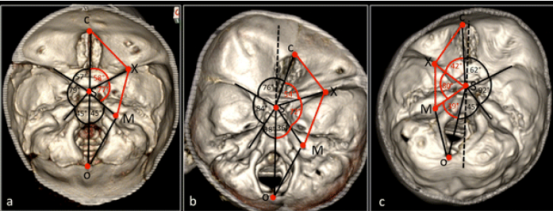

图 4:对患有先天性斜头畸形的婴儿进行了颅底形态测量分析,根据颅底畸形的严重程度将这些婴儿分为三个亚组:IIa 组、IIb 组和 III 组。研究使用 3D-CT 图像(图 a、b、c 分别对应 IIa 组、IIb 组和 III 组)进行分析。

C:筛骨 crest 的前缘S:鞍结节的中心O:枕骨大孔的后缘(opisthion)X:小翼的剑突(xiphoid)M:内听道(internal acoustic meatus)这些标志点用于将颅底分为两个半颅底。

前颅窝长度(ACF):C 到 X 的距离(CX)中颅窝长度(MCF):X 到 M 的距离(XM)后颅窝长度(PCF):M 到 O 的距离(MO)

前颅窝角(ACF 角):CSX 角(CSX^)中颅窝角(MCF 角):XSM 角(XSM^)后颅窝角(PCF 角):MSO 角(MSO^)

IIa 组、IIb 组和 III 组:前颅窝(CX)和中颅窝(XM)的长度在矢状缝融合侧均显著缩短。前颅窝角(CSX^)和中颅窝角(XSM^)表现出不对称。

IIb 组和 III 组:后颅窝角(MSO^)表现出不对称。